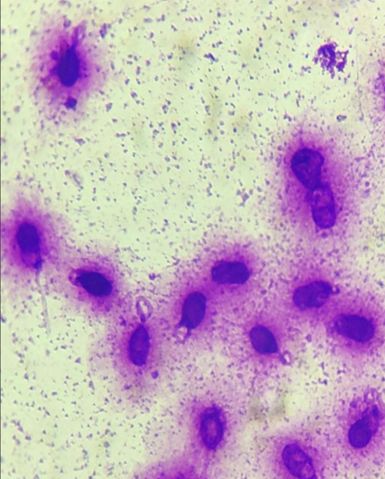

Морфология по крюгеру

Оценки морфологии сперматозоидов. Ценность оценки морфологии не только в ограниченных прогнозах в отношении самопроизвольной беременности или исхода эко, но ещё больше это диагностическая информация о функциональном состоянии мужских репродуктивных органов, в первую очередь яичек и придатков яичка.

Индекс тератозооспермия (ИТЗ)

Аномальные сперматозоиды:

- более низкий потенциал оплодотворения;

- с повышенной фрагментацией ДНК;

- с повышенной частотой структурных хромосомных аберраций;

- с незрелым хроматином;

- с анеуплодией.